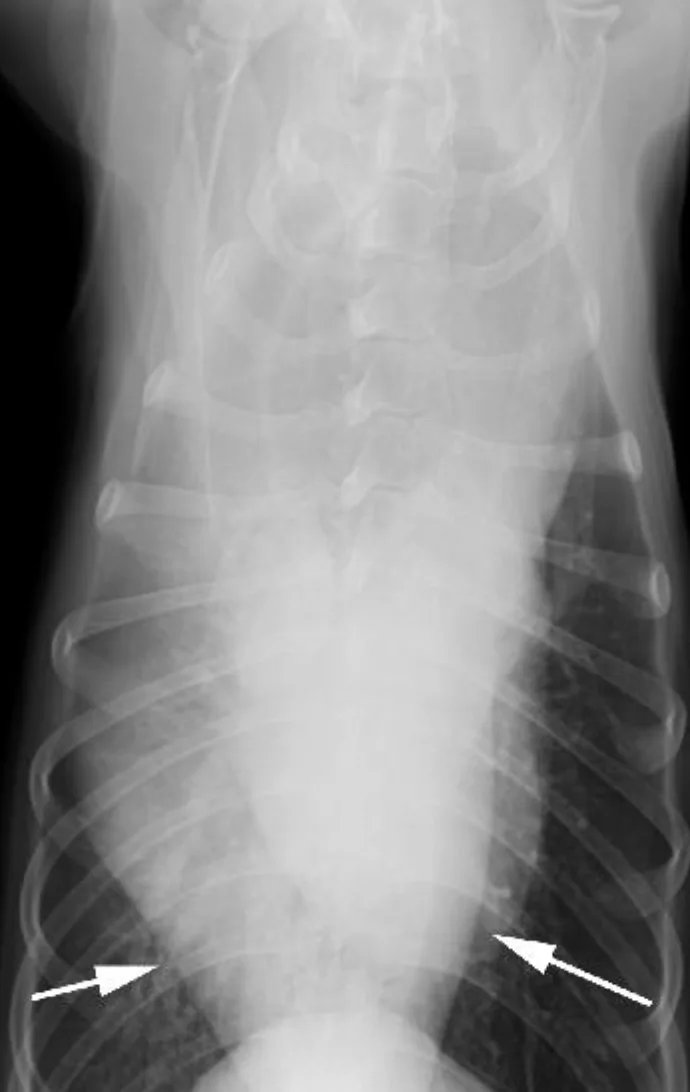

If there is an extrapleural sign, a mass lesion (eg, fractured rib, rib tumor) is pushing the parietal pleura into the pleural space (Figure 4). An anatomic variant that routinely results in an extrapleural sign is the costochondral junction of chondrodystrophic dogs, such as the basset hound or the dachshund.

Extrapleural sign (arrow) in a 10-year old basset hound, secondary to the enlarged costochondral junctions and medial deviation of the costal cartilages